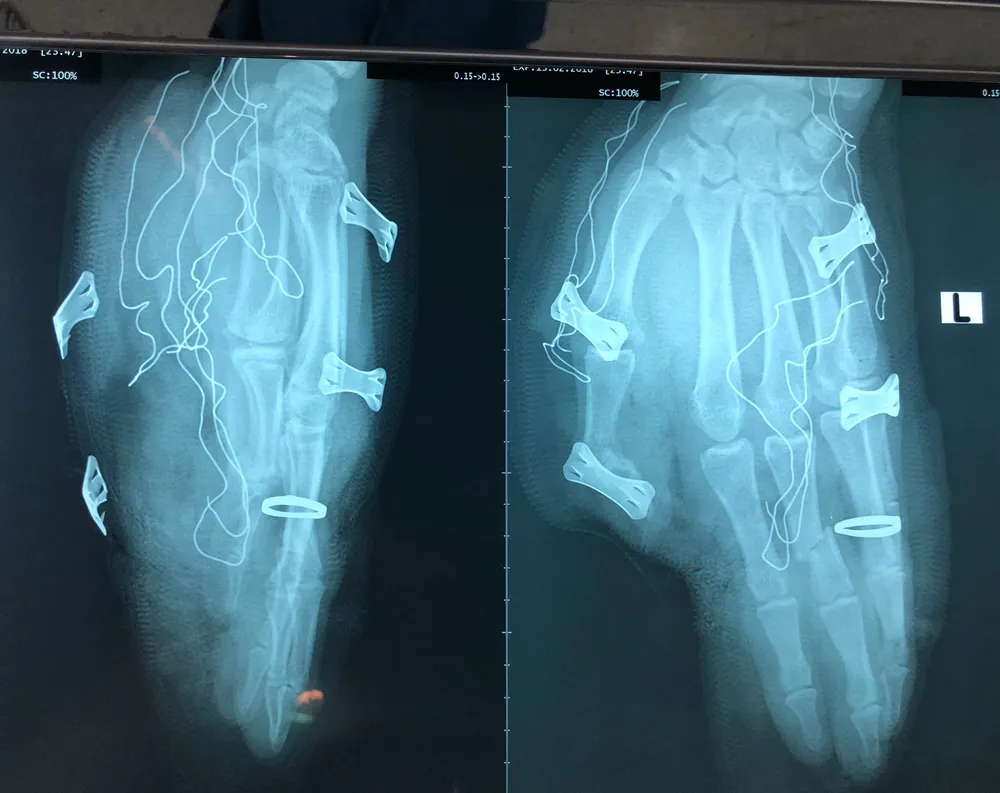

Kết quả chụp X quang cho thấy bàn tay trái anh S. bị trật hở khớp ngón và gãy xương đốt. Ảnh: HÒA VÕ